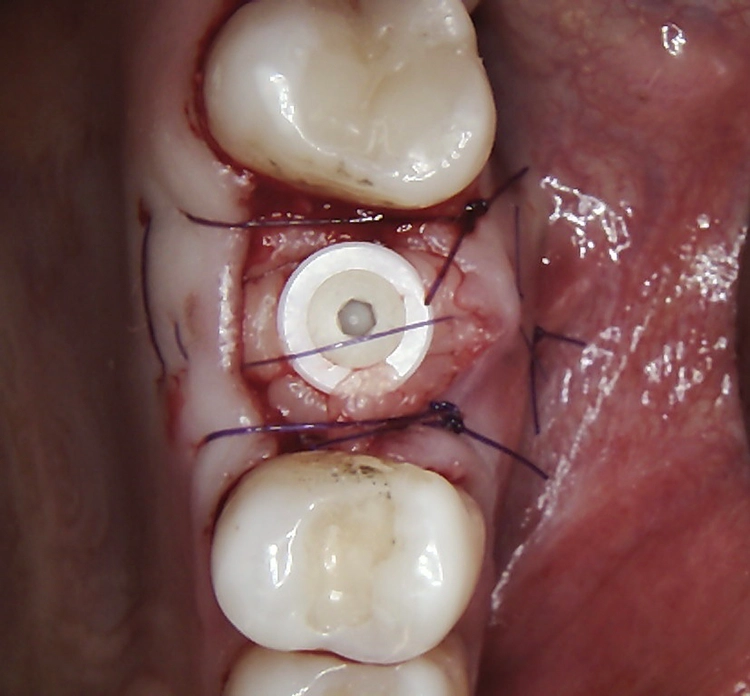

Bei dem balkonförmigen Implantat blieben die Alveolarkämme und der Kronenansatz erhalten (Abb. 4c und d). Der Spalt zwischen dem Implantat und der bukkalen Lamelle wurde mit A-PRF und einem Kollagenblock aufgefüllt, so dass keine zusätzliche Knochenaugmentation erforderlich war. Zusätzlich wurden PRF-Matrizen um, über, unter und neben dem Implantat im Knochen-Implantat-Raum positioniert (Abb. 1 bis 4b). Außerdem kam eine optionale Einheilscheibe (6 x 8 mm) zum Einsatz, um das Kollagen und die PRF zu sichern (Abb. 3b). Die Implantate zeigten bei einem Drehmoment von 35 Ncm Stabilität, welche mit dem Periotest-Gerät von Medizintechnik Gulden getestet wurde. Die Werte des Implantatstabilitätstests, die im Bereich von –8 bis 0 lagen, wurden als ideal für die Belastung angesehen (Tab. 3).

Abb. 2: Repräsentativer Fall von ABH Grad B Septus Typ II. a) Ansichten vor der Installation. Röntgenaufnahme der periapikalen Läsion an einem wurzelkanalbehandelten Molaren und klinische Ansicht der Typ-II-Socket nach der Extraktion. b) Die Ansichten nach der Installation zeigen das Implantat innerhalb des interradikulären Septums und das über dem Implantat platzierte A-PRF. c) Nachuntersuchungen nach 10 Tagen bzw. 2,1 Monaten. Die Röntgenaufnahme zeigt die Knochenbildung zwischen der Sinusmembran und dem apikalen Teil des Implantats. d) Jüngste Nachuntersuchung nach Einsetzen der Prothese.